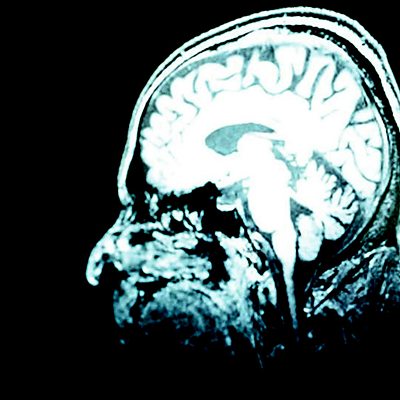

Deep Brain stimulation is a brain surgery technique involving electrodes being inserted to reach targets deep inside the brain. Those targets are then stimulated via the electrodes which are connected to a battery powered pacemaker surgically placed under the person's collar bone. Geoff Watts finds out how the technique has been used successfully for treating the movement disorders of Parkinson's disease, in patients with severe, intractable depression, in chronic pain and how it's also being trialled to see if it can also be successful in treating Obsessive Compulsive disorder, Tourette's syndrome and other disorders. Geoff meets patients who have had their lives changed by having Deep brain stimulation. He also meets the surgeons at the operating table to find out how it works. At the moment no one has all the answers but one psychiatrist he meets says the success of Deep Brain stimulation means we should radically change the way we understand how the brain works. That the brain is governed by electrical circuitry rather than a chemical soup of neurotransmitters.